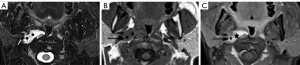

Schwannomas are benign tumors arising from Schwann cells surrounding peripheral nerves. Schwannomas in the carotid space most commonly stem from the vagus nerve. The tumor is usually a sharply demarcated round or oval mass with hypo-, iso-, or hyper-attenuation. Cystic degeneration, xanthomatous change, or areas of relative hypocellularity adjacent to densely cellular or collagenous regions usually contribute to heterogeneity of the tumor (Figure 1) (9,10). Schwannomas are hypovascular tumors, but in dynamic scans, they can show marked enhancement due to pooling of contrast agent resulting from poor venous drainage (11). More often, schwannomas demonstrate a variable degree of enhancement, most commonly patchy enhancement (Figures 2-7).

Due to its location between the vein and artery in the carotid space, schwannomas of the vagus nerve tend to separate the artery and vein, usually displacing the CCA/ICA medially and the IJV laterally (Figures 2,3) (12). Some schwannomas of the vagus nerve may displace the IJV and ICA/CCA in a posterior direction without splaying them and there is usually separation between the artery and vein (Figure 4). The cervical sympathetic chain runs in a fascial reflection posterior and slightly medial to the carotid space. Hence, schwannomas of the sympathetic chain tend to displace the IJV and CCA/ICA together, usually anteriorly and laterally (Figure 5) (5). A large schwannoma of the sympathetic chain may distort the surrounding anatomy and result in a posterior displacement of the carotid vessels without separation of the artery and vein (Figure 6) (13,14). Occasionally, a schwannoma of the cervical sympathetic chain may splay the internal and external carotid arteries at the carotid bifurcation but without encasing the arteries (Figure 7) (5). In these regards, the position of the tumor relating to the vessels in the carotid space is more important than the direction of vascular displacement. There has also been a reported case of schwannoma arising from the glossopharyngeal nerve in the carotid space causing posterior displacement of the ICA (15).